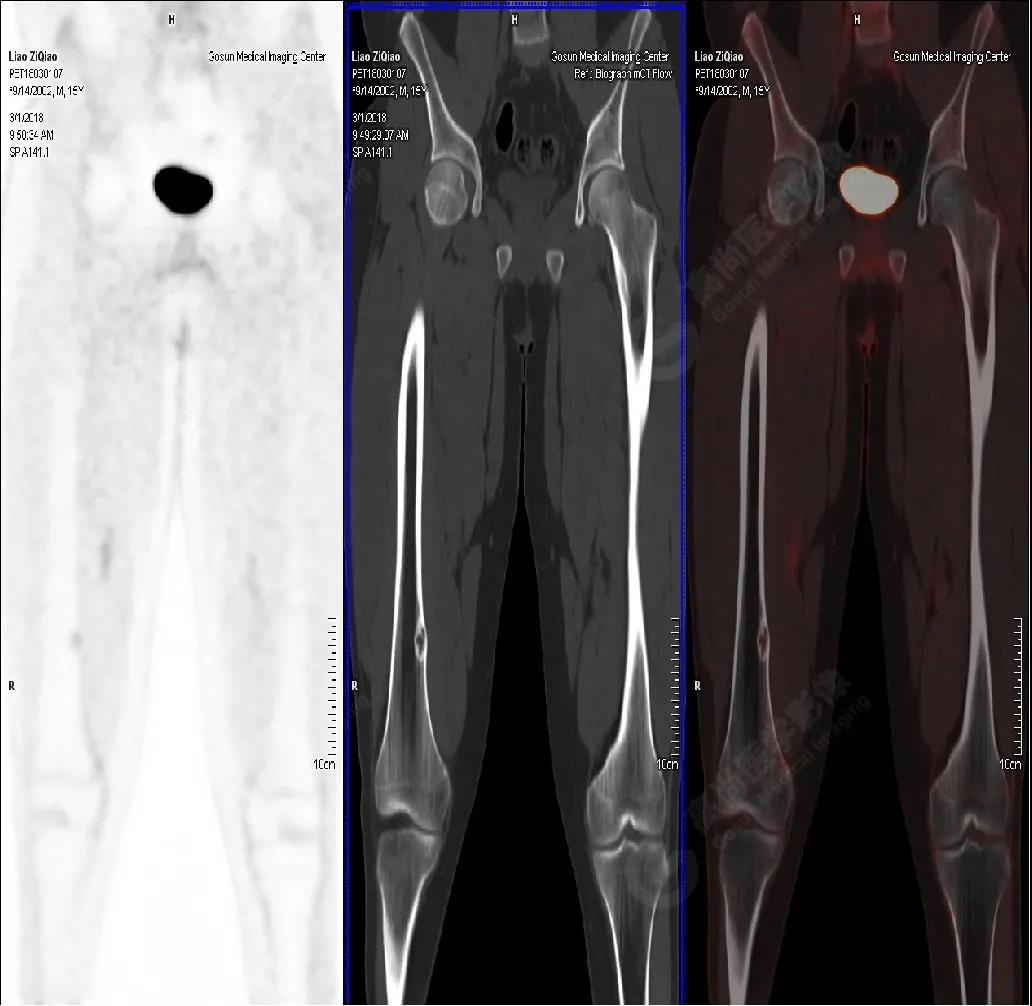

男性,15歲,右側(cè)大腿疼痛1月余,DR提示右側(cè)股骨下段囊性低密度占位。既往無外傷史、否認(rèn)肝炎、結(jié)核及手術(shù)史。

PET/CT檢查

PET/CT表現(xiàn)

右側(cè)股骨下段(內(nèi)側(cè)緣)見骨皮質(zhì)局限性膨脹性破壞,突入髓腔內(nèi),邊界清楚,邊緣硬化,灶內(nèi)見纖維骨嵴,放射性攝取略增高,SUV最大值為1.4,平均值為1.3。

PET/CT診斷

右側(cè)脛骨良性骨病,以非骨化性纖維瘤可能性大。

病理診斷

隨訪結(jié)果:活檢病理確診非骨化性纖維瘤。